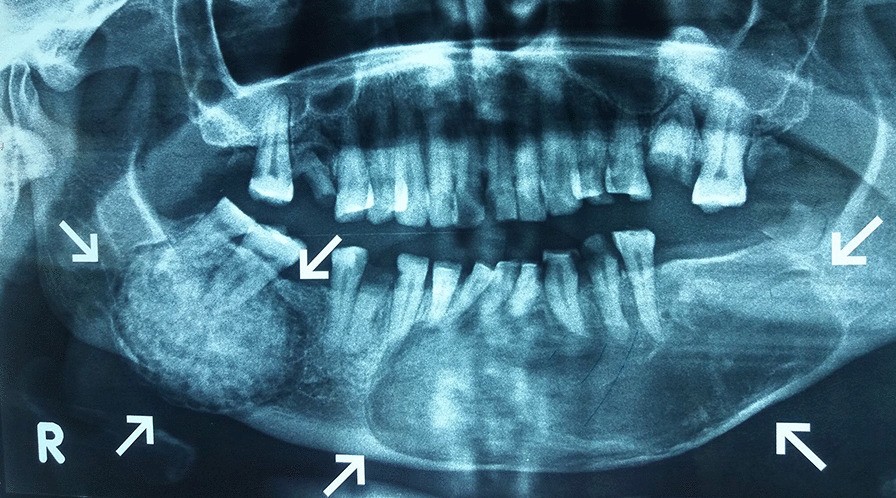

Cementoblastoma

Cementoblastoma - Wikipedia Apical Radiopacities - Radiodontics Cementoblastoma: Features, Diagnosis, and Treatment Cementoblastoma. Classic appearance of a sclerotic tumor fused ... ❇ Benign Cementoblastoma Radiology: ▶ Location: → 78% in ... Cementoblastoma